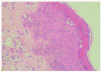

La biopsia cutánea mostró una epidermis con hiperqueratosis homogénea sin paraqueratosis y mínimo infiltrado inflamatorio. Se observaban múltiples amastigotes en el interior de los queratinocitos, con degeneración vacuolar y libres a todos los niveles de la epidermis, incluyendo la capa granulosa y entre la queratina de la capa córnea. También se observaron en menor proporción en el conducto excretor ecrino y en el acrosiringio. En la dermis y la hipodermis se apreciaban múltiples organismos intra y extracelulares, entre los haces de colágena, alrededor de las glándulas ecrinas, entre los adipocitos y alrededor de los vasos sanguíneos (figs. 2 y 3).

Fig. 2.--Numerosas leishmanias a todos los niveles de la epidermis, incluida la granulosa y entre la queratina de la capa cornea. (Hematoxilina-eosina, x400.)